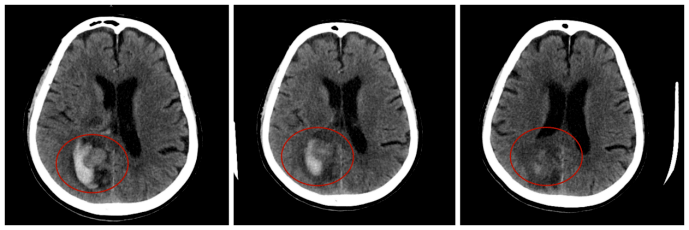

79岁的欧大爷在家中不慎摔倒后突发急性脑梗塞,短短1天内病情急转直下,出现脑梗死出血转化。莆田福德医院神经内科团队迅速启动多学科会诊,通过精准的影像评估、个体化的诊疗方案,成功将欧大爷从危险边缘拉回。如今,他不仅能下地行走,更重拾了与家人共享天伦的幸福时光。这例精准救治案例,正是福德医院神经内科“专业、高效、人文”医疗理念的生动诠释。